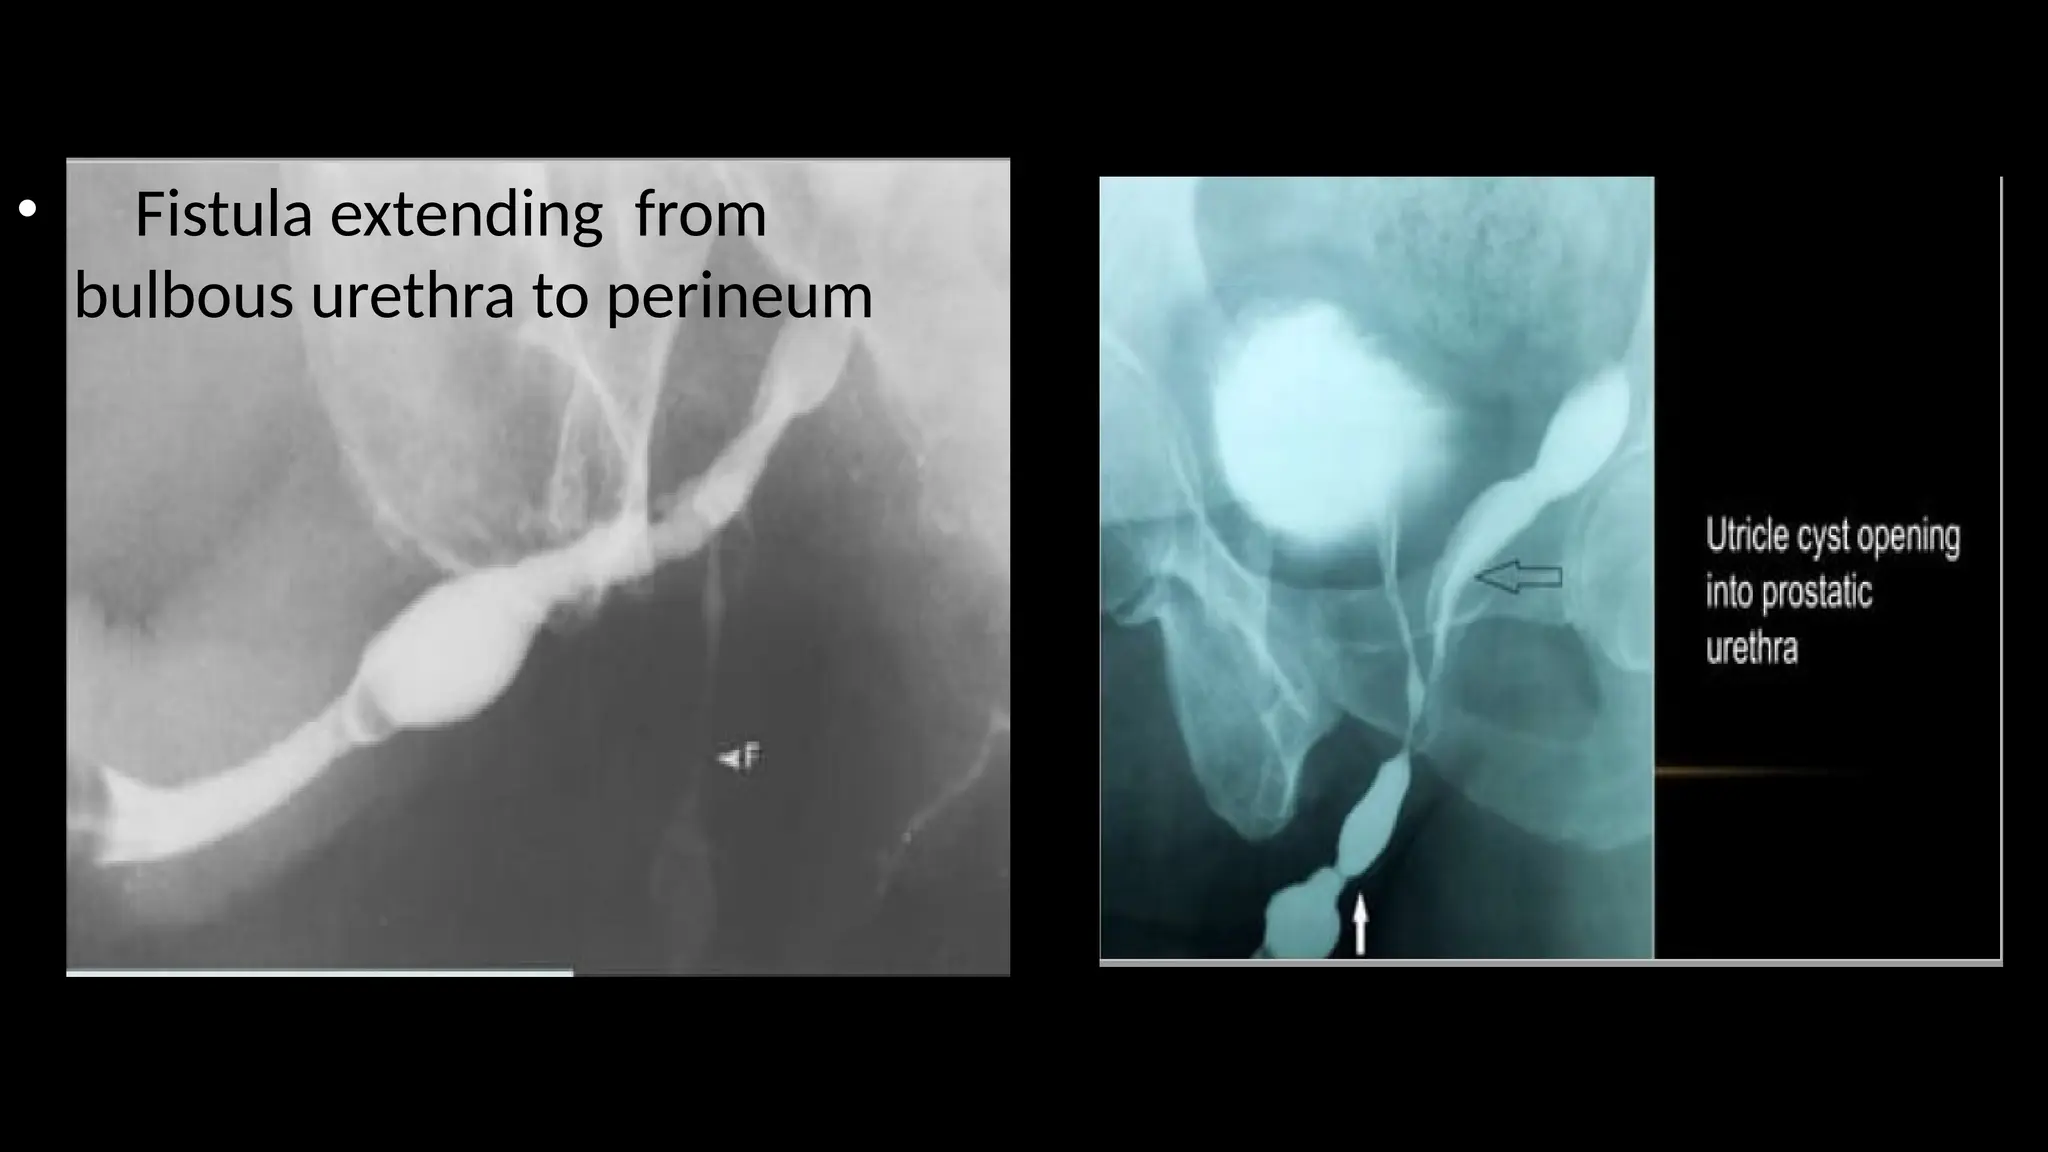

• Fistula extending from

bulbous urethra to perineum

• Fistula extendingfrom bulbous urethra to perineum